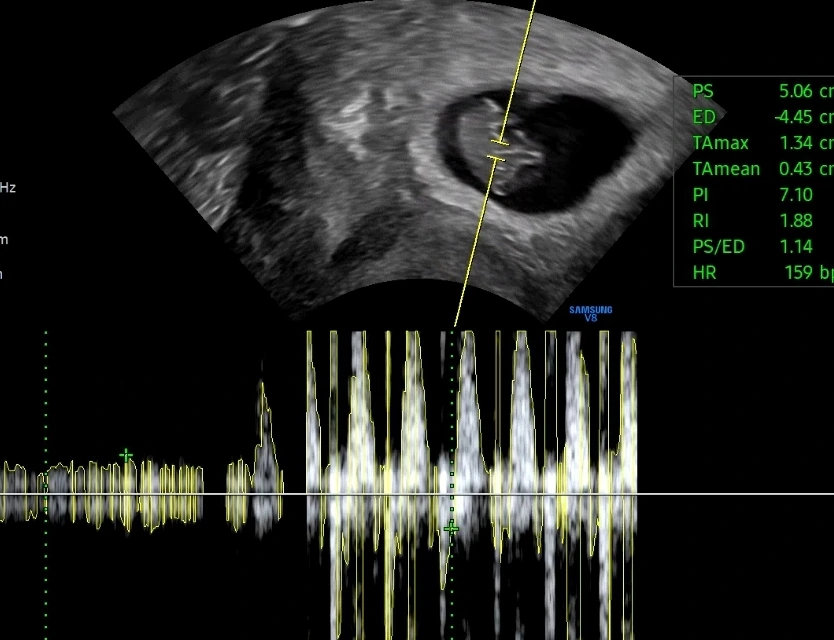

오빠와 사이좋게 손잡고 병원에 갔다. 오늘은 아기의 심장소리를 들을 수 있다고 선생님께서 말씀하셨다. 지난 번에 작은 점이었던 아기였는데, 오늘은 무언가 많은 것들이 생겼다 (?) #임신7주차초음파 아직 사람의 형태를 갖추고 있지는 않지만 꼬리같은 것도 보이고, 외계인 같기도 하다. (ㅎㅎㅎ)

남편이랑 나는 심장소리를 듣고 너무너무 신기했는데 동시에 너무도 얼떨떨했다. 심장 소리를 들을 때 살짝 울컥하긴 했는데 스멀스멀 올라고 있는 입덧으로 나는 기운이 많이 떨어진 상태였고, 평소에 입던 바지가 답답해서 배가 조여오는 불편함 등으로 컨디션이 좋지 않았다. 우리 서로 아기 심장소리를 듣고 마음은 참 기뻤는데 내가 컨디션이 안좋아서 남편도 나를 걱정하느랴 아기에 대한 기쁨을 온전히 느끼지 못했다.

임신7주차 초음파 & 심장소리